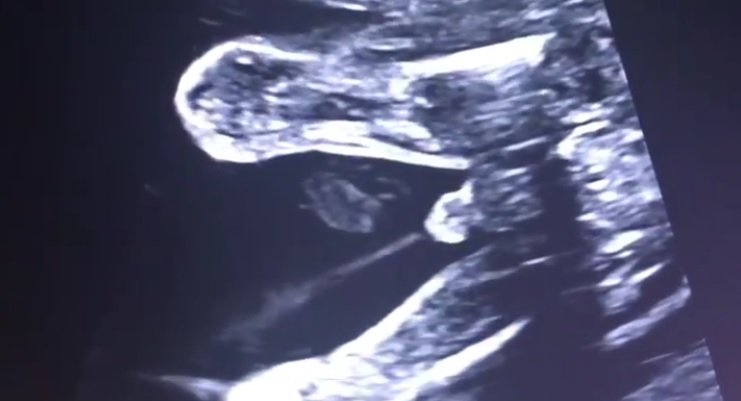

Dacă vă întrebați dacă un bebeluș face pipi în uterul mamei, ei bine, veți primi răspunsul cu o mică filmare a unui medic din Turcia, care suprinde un moment unic la o ecografie. Este vorba despre Dr. Ümit Korucuoğlu, un medic ginecolog obstetrician din Ankara, Turcia, care dețin un cont foarte popular pe Instagram, urmărit de peste 28,000 de persoane.

Medicul ginecolog-obstetrician ne confirmă ceea ce poate, mulți dintre noi, doar bănuiam: cea mai importantă componentă a lichidului amniotic este... urina. Iar bebelușii chiar fac pipi în uterul mamei. Dacă majoritatea mamelor sunt norocoase să vadă un gest simpatic al bebelușului lor nenăscut, în timpul unei ecografii de sarcină, iată că pacienta medicului din Turcia a avut parte de ceva mult mai neobișnuit: momentul în care micuțul ei face pipi.

În video-ul postat de Dr. Korucuoğlu pe Instagram se poate vedea clar acest moment. ”Să începem ziua cu o mică surpriză. Putem vedea răspunsul la întrebarea dacă bebelușii urinează în pântecul mamei în acest video. Mai ales udpă săptămâna 20 de sarcină, cel mai important component al lichidului amniotic este urina fetală. Măsurând lichidul amniotic în timpul ecografiilor putem vedea că rinichii bebelușului sunt sănătoși. Astfel, este confortabil să vedem că bebe produce suficientă urină.”, scrie medicul pe Instagram.